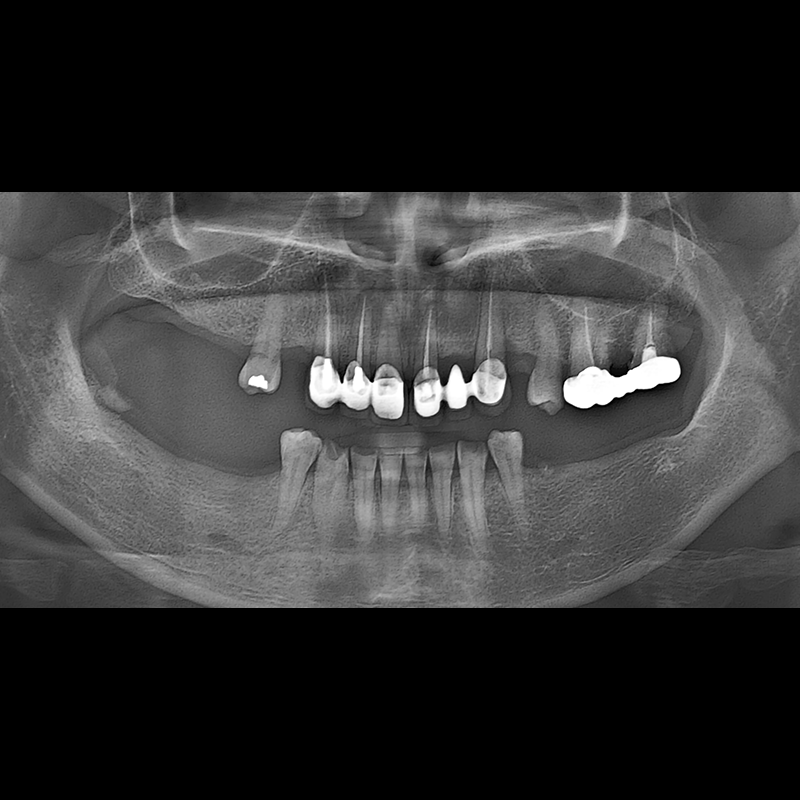

BEFORE AFTER

임플란트 전후사진 2025.05.30

결손된 치아 부분과 살리기 힘든 치아 위치에 임플란트를 식립하였습니다.